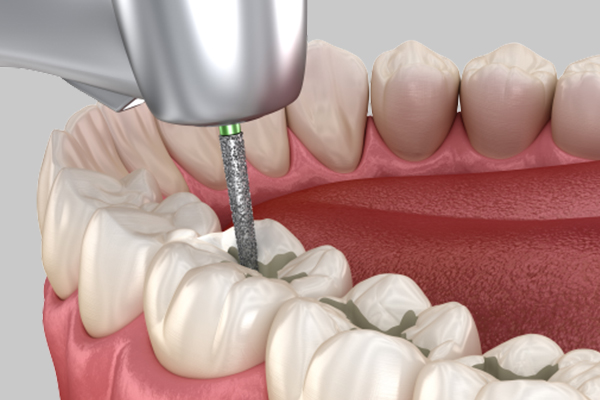

Pulpitis

Inflammation has progressed to the dental pulp, causing severe pain that may become difficult to tolerate.

Root Canal Treatment + Crown